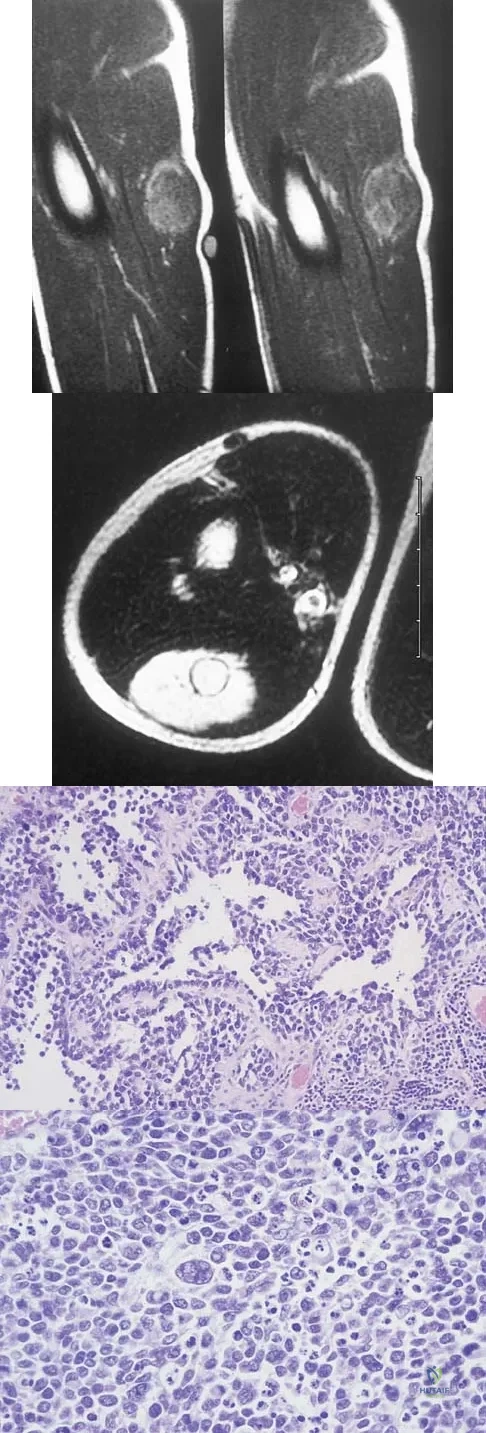

Question 37

A 7-year-old girl has had a painful forearm for the past 2 months. Examination reveals fullness on the volar aspect of the forearm. Radiographs and an MRI scan are shown in Figures 42a through 42c. Biopsy specimens are shown in Figures 42d and 42e. What is the most likely diagnosis?

Explanation